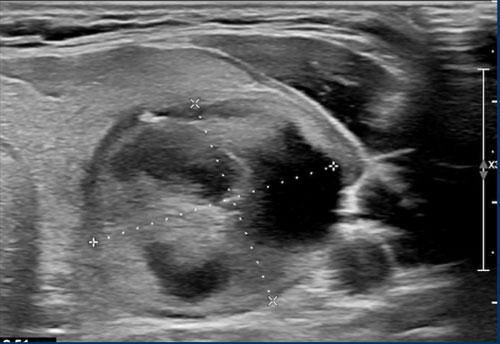

Ca 2

Xem hình ảnh và xác định điểm TI-RADS.

Cuộn hình ảnh để xem điểm TI-RADS.

Tiến hành phân tích bên dưới.

Điểm TI-RADS: 1 điểm cho sự hiện diện của vôi hóa thô.

Tổn thương này được phân loại TI-RADS 5, chủ yếu do tính chất giảm âm rõ rệt.

Nếu tổn thương có chiều cao lớn hơn chiều rộng, điều này sẽ cộng thêm 3 điểm.